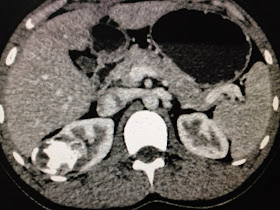

MSCT of chest-abdomen detected left diaphragm in rupture and the great omentum going up to the lung (see CT foto).

It was an emergency case with no history of trauma.

Laparo and thoracoendoscopy detected a big defected wound of posterior left diaphragm; great omentum going up to the lung.

It is BOCHDALEK HERNIA, need to suture for repairing left diaphragm (see foto).